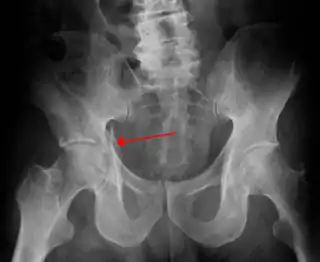

![]() Radiografía en la que puede visualizarse una fractura de acetábulo | ||

La fractura de acetábulo o fractura de cavidad cotiloidea, es un tipo de fractura ósea que afecta a la cavidad cotiloidea en la pelvis. No debe confundirse con la fractura de fémur, en la fractura de acetábulo el fémur permanece indemne, salvo que exista lesión combinada.[1]